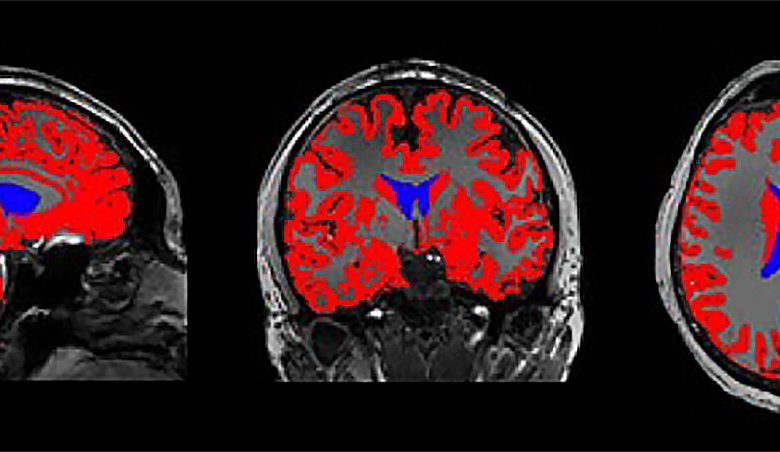

Imagem de ressonância magnética do cérebro com os ventrículos laterais coloridos em azul. Os ventrículos estão cheios de líquido cefalorraquidiano. Crédito: RIKEN

O significado exato do sinal de fMRI vindo do cérebro – especificamente dos ventrículos laterais – permanece um mistério para estudos futuros. Os sinais de fMRI dependem das propriedades magnéticas da hemoglobina no sangue, mas não há nenhuma no líquido cefalorraquidiano. O sinal pode estar relacionado a uma combinação de processos associados à atividade cerebral e à remoção de resíduos.